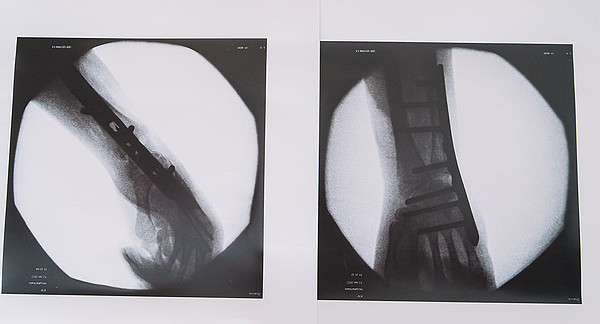

Врачи Центра травматологии, ортопедии и нейрохирургии помогли восстановить подвижность конечностей девочке с ДЦП